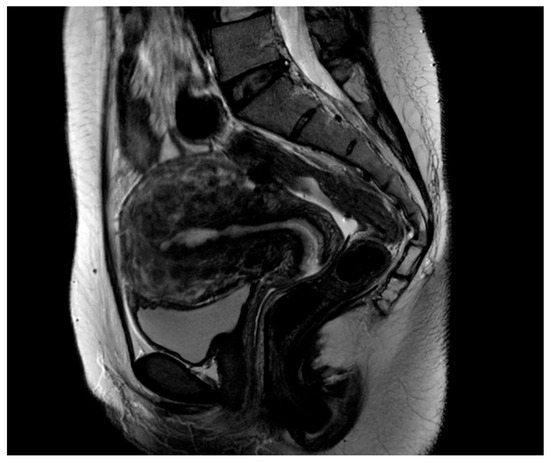

Clinical Outcomes of Conservative Surgery for Diffuse Uterine Leiomyomatosis: Preliminary Experience of 17 Cases in a Single Center

2. Materials and Methods